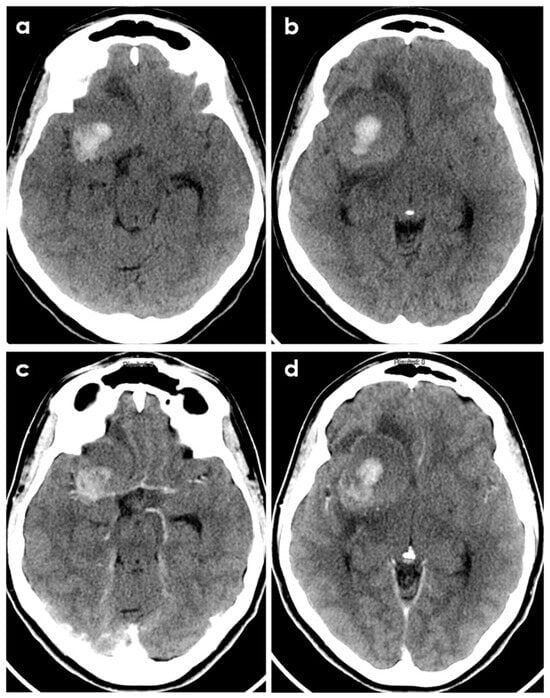

- Case A had a small right frontal cortical hemorrhage with subarachnoid extension and leptomeningeal enhancement over the right hemisphere on post-gadolinium T1-weighted sequences, persisting over the following 3 months together with accumulation of small acute infarcts and persistent leptomeningeal enhancement; CTA was normal, and the diagnosis was achieved by brain biopsy.

- Case B had a right cerebellar hemorrhage on anticoagulant therapy and underwent emergent posterior fossa decompression. In the early follow-up, a new left cerebellar hemorrhage and an acute left pontine infarction occurred; the diagnosis was provided by histopathologic examination of the surgically evacuated tissue.

- Case C had a right parietal lobar hemorrhage with subarachnoid extension, multiple small disseminated acute and subacute infarcts and small rounded sulcal hyperintensities on a fluid-attenuated inversion recovery sequence (dot sign); the diagnosis was provided by the angiographic pattern involving distal branch arteries.

- Case D had a right temporal lobe hemorrhage with small disseminated acute infarcts and chronic microbleeds; diagnosis was provided by angiography, and biopsy was negative.